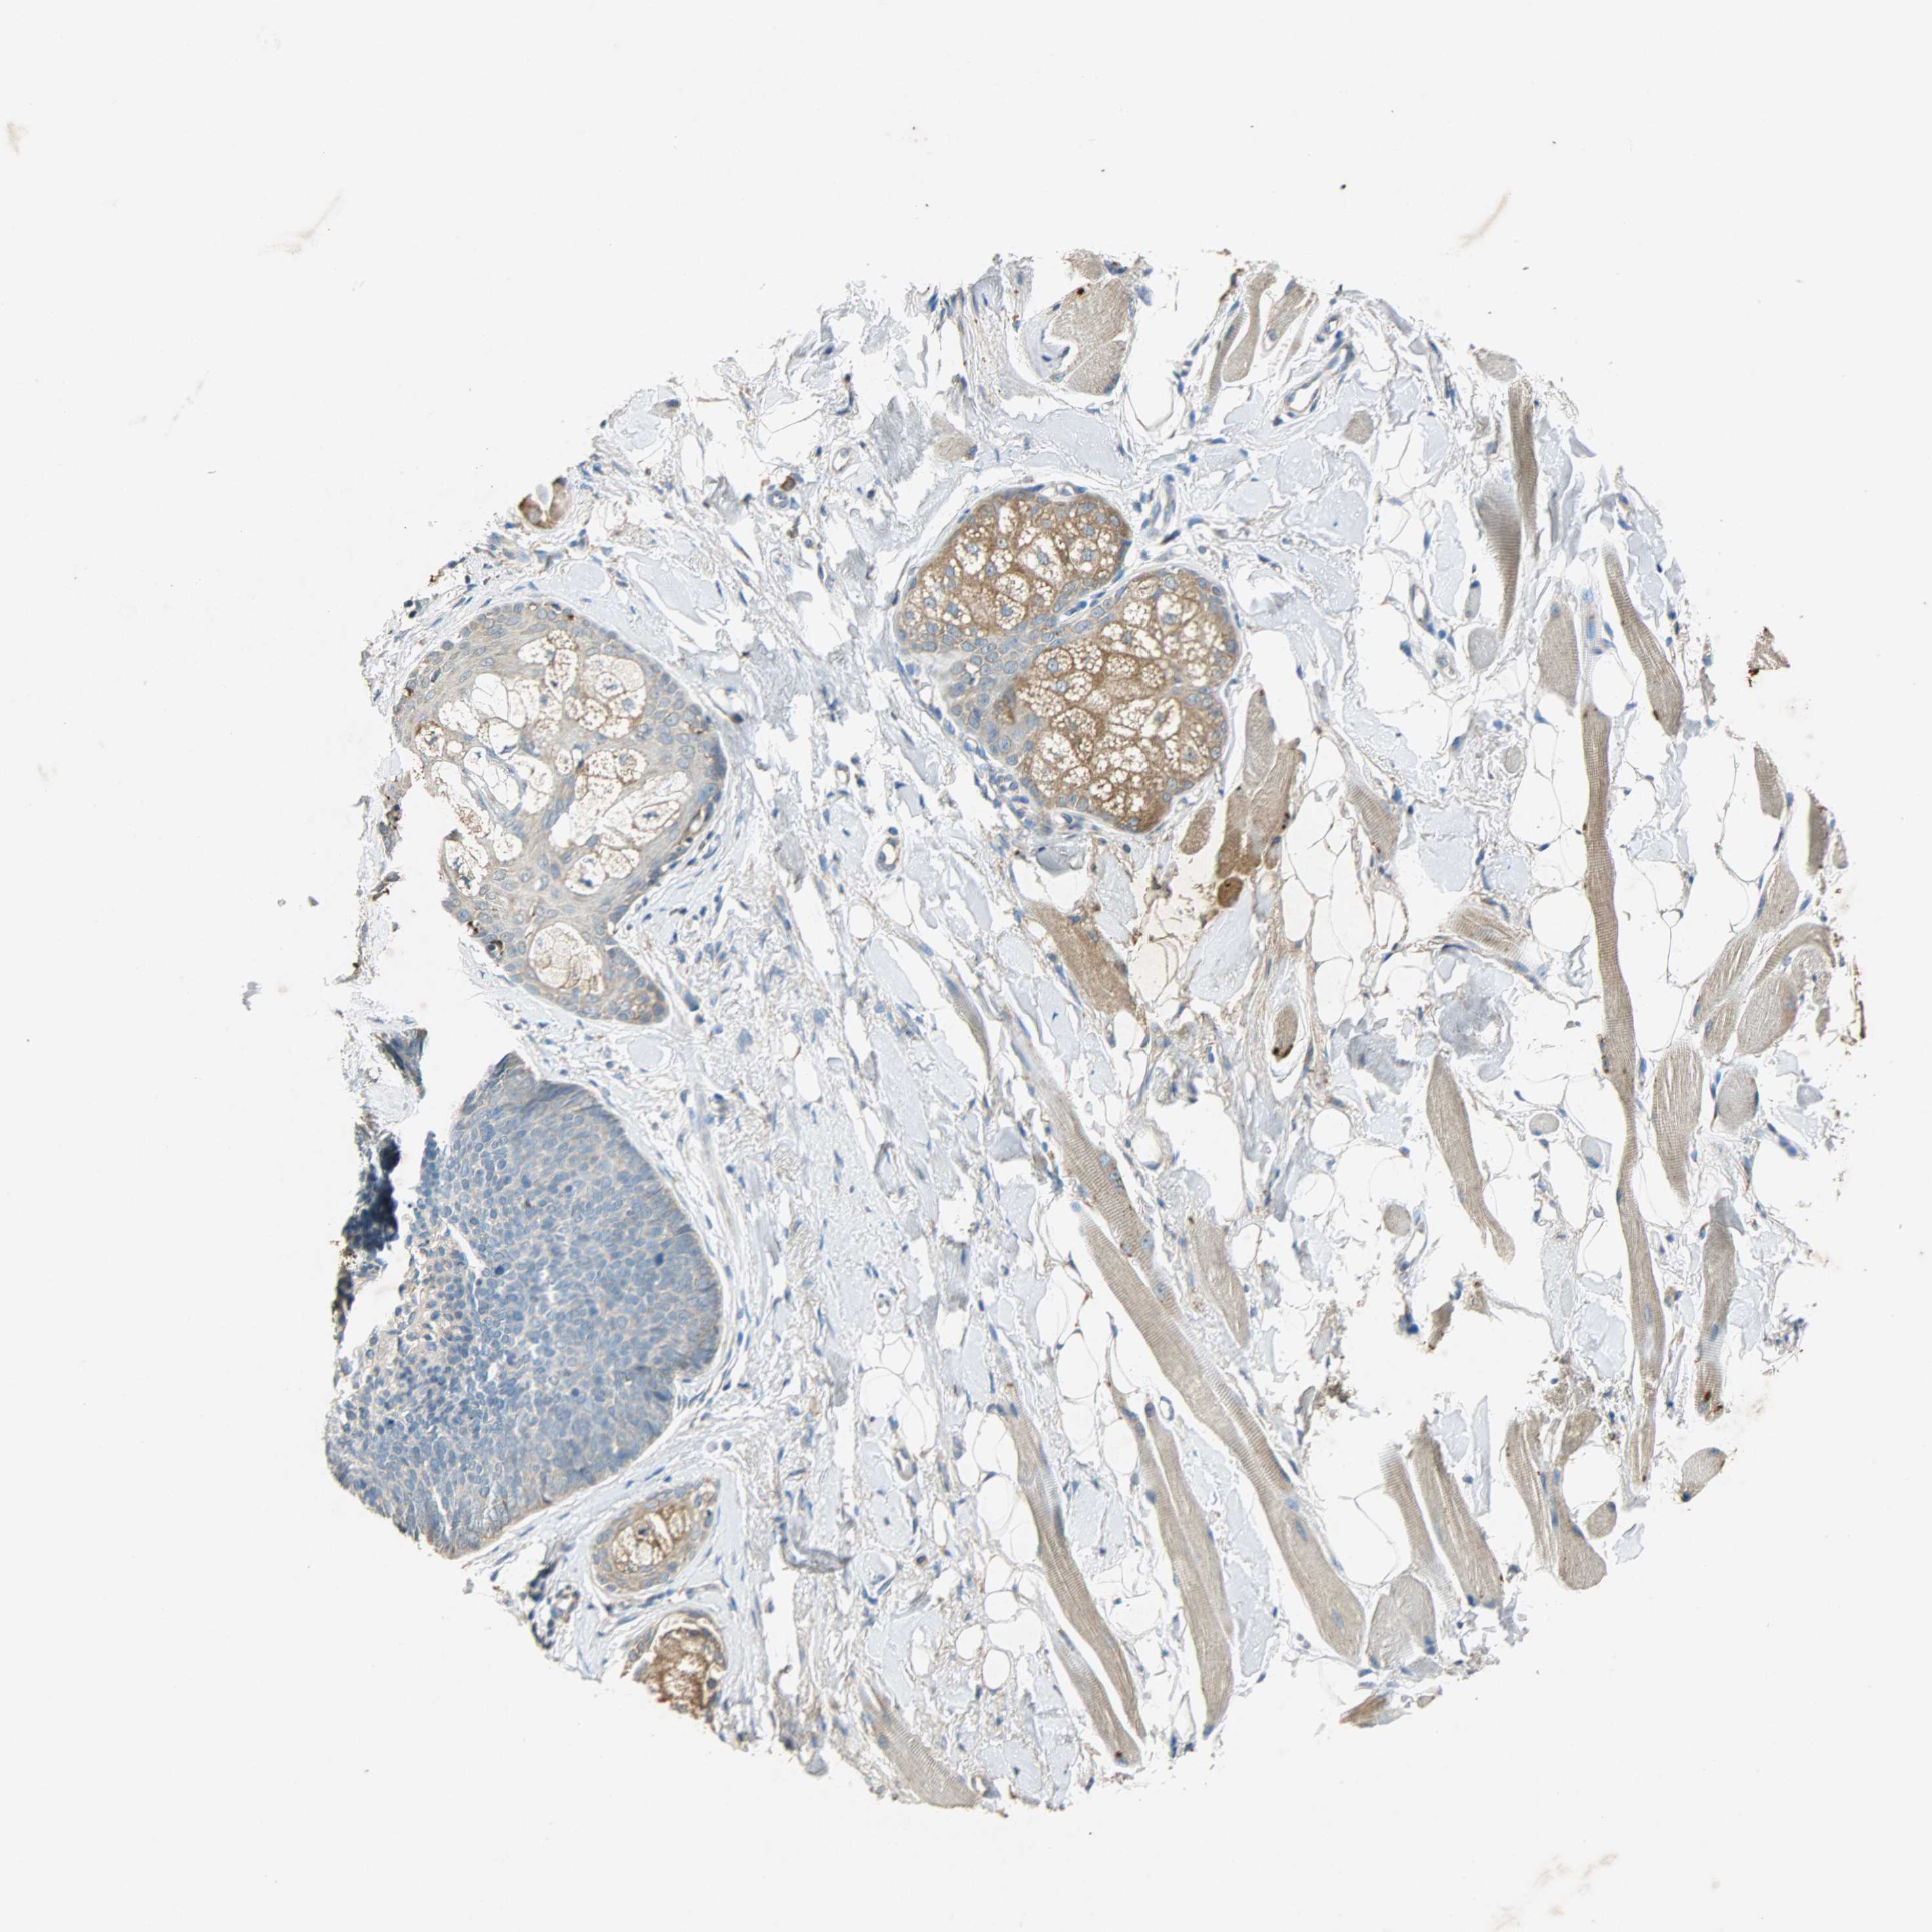

Basal cell and squamous cell cancer

SKIN CANCER - Protein expressioni

A mouse-over function shows sample information and annotation data. Click on an image to view it in a full screen mode. Samples can be filtered based on level of antibody staining by selecting one or several of the following categories: high, medium, low and not detected. The assay and annotation is described here.

Each image is clickable and will lead to virtual microscopy that enables deeper exploration of all samples and also displays staining intensity scores, fraction scores and subcellular localization as well as patient and tissue information for each sample.

Antibody HPA038845

Antibody HPA038846

Antibody CAB005221

Squamous cell carcinoma, NOS

Squamous cell carcinoma, metastatic, NOS